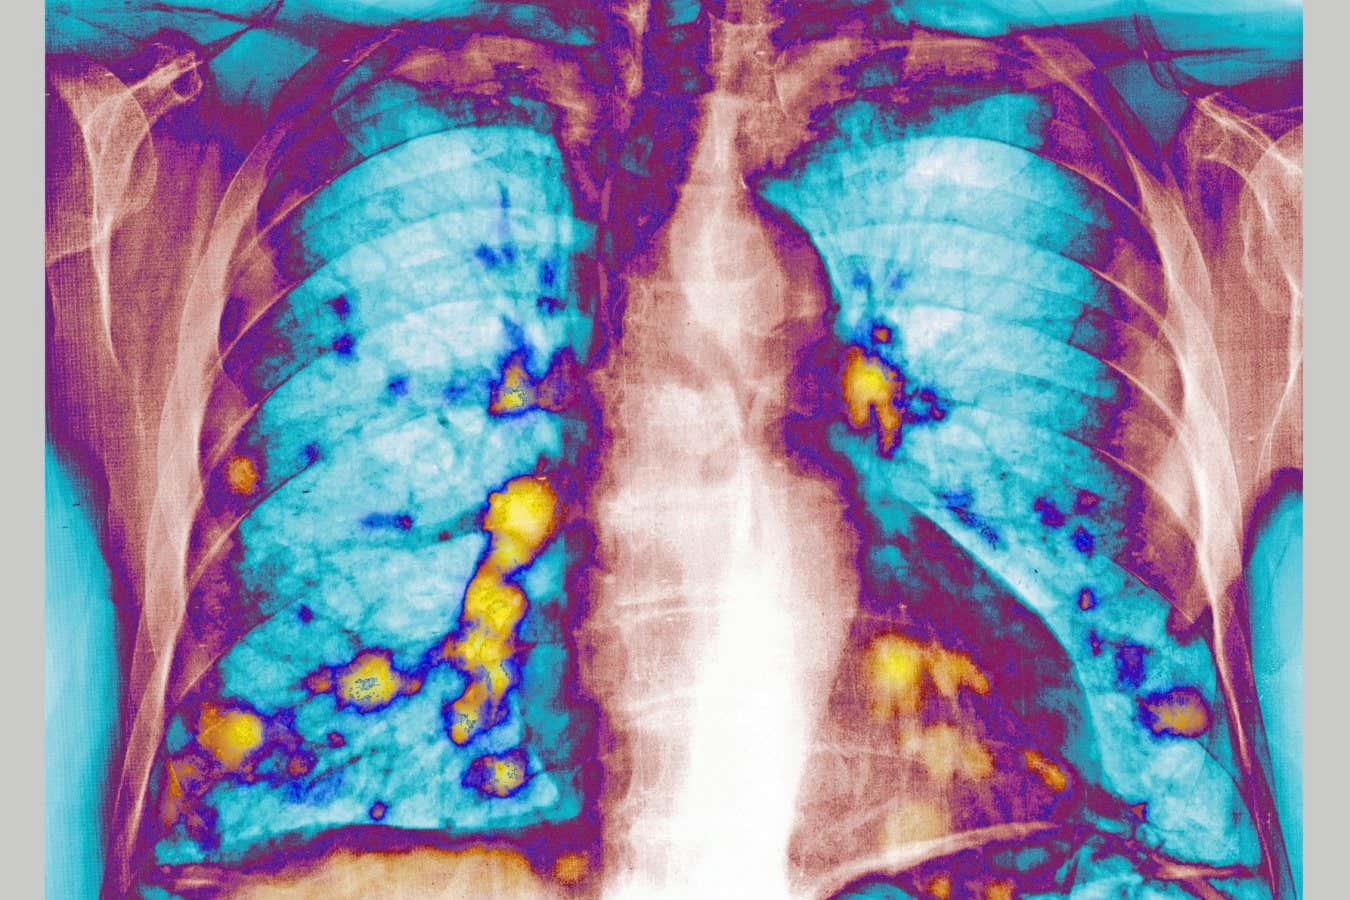

Catching a cold can delay cancer from spreading to the lungs

Infecting mice with RSV, a common virus that causes cold-like symptoms, prevented breast cancer cells from reaching their lungs. This was due to the release of proteins that stop viruses from replicating in the lungs also making it harder for cancer cells to seed new tumours